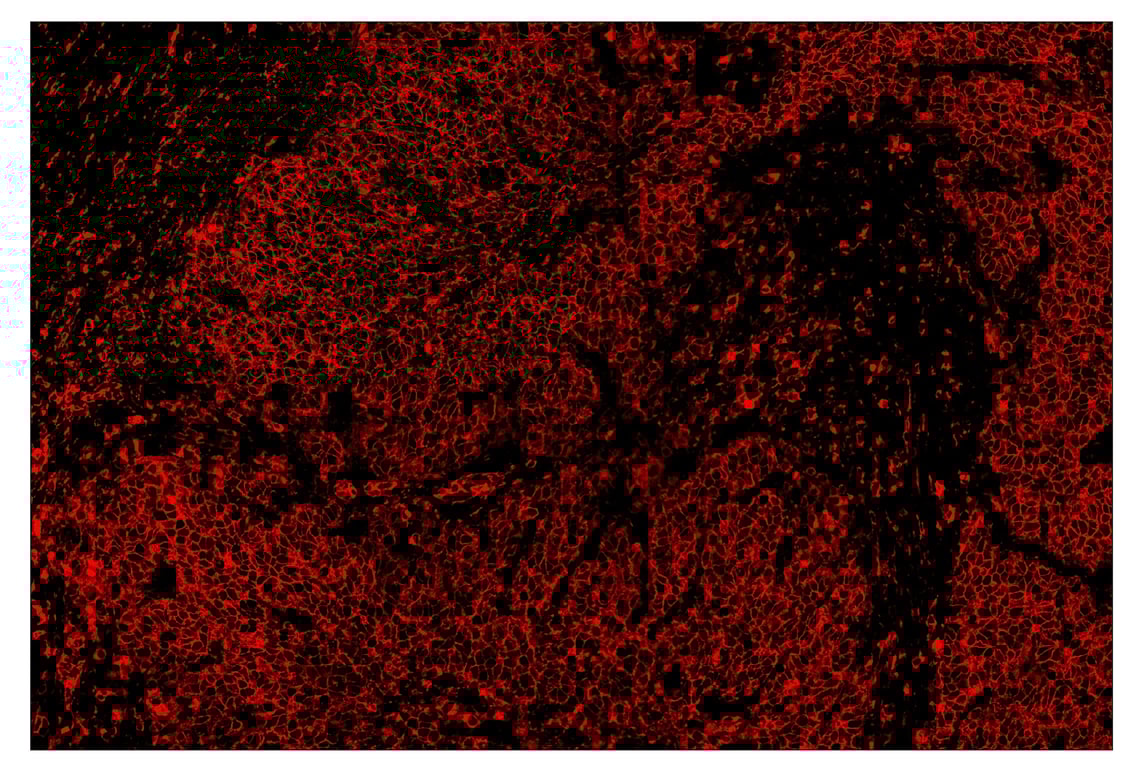

SignalStar™ immunohistochemical analysis of paraffin-embedded human gastric adenocarcinoma using HLA-DRA (E9R2Q) & CO-0023-647 SignalStar™ Oligo-Antibody Pair #41373 (red). All fluorophores have been assigned a pseudocolor, as indicated. Staining was performed on the BOND RX by Leica Biosystems.

Immunohistochemistry Image 4: HLA-DRA (E9R2Q) & CO-0023-647 SignalStar<sup>™</sup> Oligo-Antibody Pair